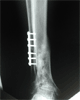

Follow

Up

Good bony union with preservation of ankle joint alignment

Result

Good return ankle motion